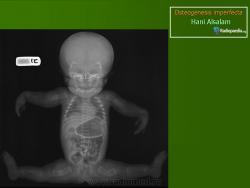

Клиническая картина зависит от типа заболевания, возраста его проявления и от тяжести поражения скелета и других органов. Если болезнь выявлена у новорожденного, то это, скорее всего, несовершенный остеогенез типа II (традиционное название - врожденный несовершенный остеогенез). Прогноз в этом случае крайне неблагоприятный. При несовершенном остеогенезе типа II ребенок рождается со множественными переломами длинных трубчатых костей; после заживления переломов кости укорачиваются, утолщаются и деформируются. Рождение мертвого плода или ранняя смерть новорожденного обычно вызваны дыхательной недостаточностью или повреждением ЦНС. При несовершенном остеогенезе типа III переломы отмечаются реже; нет врожденного укорочения и деформаций конечностей. Такие дети обычно живут несколько лет, причем деформации длинных костей прогрессируют). И в этом случае непосредственной причиной смерти обычно бывает дыхательная недостаточность. Несовершенный остеогенез типов I и IV протекает не так тяжело. Больные доживают до пожилого возраста. Повышенная ломкость костей сопровождается слабостью и разболтанностью суставов, кровоподтеками и кондуктивной тугоухостью (обусловленной плохой костной проводимостью). Для подтипов IB и IVB характерна дисплазия зубов, а именно нарушение развития эмали и дентина (dentinogenesis imperfecta). Зубы имеют янтарный, желто-коричневый или голубоватый цвет из-за нарушения образования дентина. Постоянные зубы нередко колоколообразные, суженные у шейки. Отличительная черта несовершенного остеогенеза типа I - устойчивая голубая окраска склер. Несовершенный остеогенез типа IV по клинической картине сходен с несовершенным остеогенезом типа I, но у детей младшего возраста склеры имеют нормальный белый цвет. При оценке окраски склер надо помнить, что голубые склеры могут быть и у здоровых новорожденных и грудных детей.

Тип 2 [OMIM 166210 перинатально летальная форма R или p (OMIM 259400)]. В основном формируется грубоволокнистая кость; тяжёлая летальная форма, дети рождаются мёртвыми или умирают в неонатальном периоде, имеют пониженную массу тела, короткие искривлённые конечности и множественные переломы